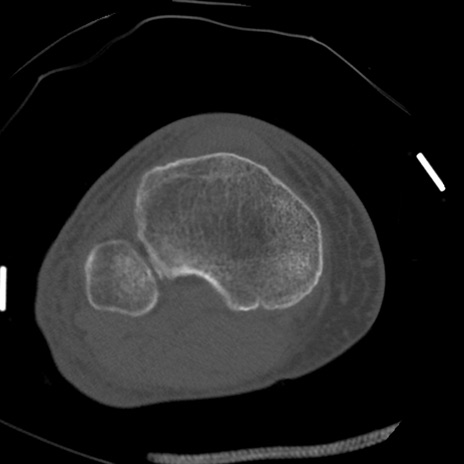

症例28 右膝関節CT(横断像)

右膝関節CT